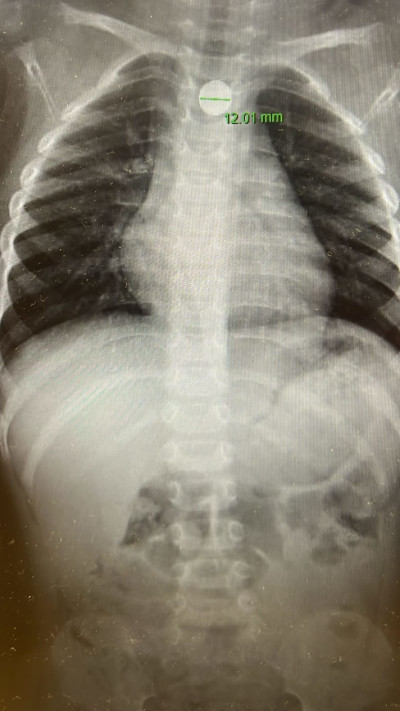

צילום רנטגן של בית החזה של הילד

צילום רנטגן של בית החזה של הילד | צילום: דוברות מרכז רפואי "מאיר" מקבוצת "כללית"

צילום רנטגן של בית החזה של הילד | צילום: דוברות מרכז רפואי ''מאיר'' מקבוצת ''כללית''

לדברי ד"ר זיפמן, "סוללה בוושט היא מצב חירום. מדובר באזור רגיש, שבו סוללות עלולות לגרום לנזק לרירית בתוך זמן קצר". הוא מסביר כי הפגיעה מתרחשת בשלושה מנגנונים: לחץ ישיר של הסוללה על הרירית, הפרשת חומרים קורוזיביים וזרם חשמלי הפוגע ברקמה. הרופאים במרכז רפואי מאיר מדגישים כי בכל חשד לבליעת סוללה – גם אם הילד נראה ללא תסמינים – יש להגיע מיד לבית החולים. ניתן למנוע מקרים כאלה באמצעות הקפדה על אבטחת הסוללות במוצרים והרחקתן מהישג ידם של ילדים.